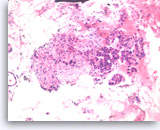

Ductal adenocarcinoma #1,

Pancreas FNA, Cell Block.

The tumor cells are pleomorphic and form poorly organized glands of variable sizes. Some of the glands are fused together. Prominent intracytoplasmic mucin is present.

40X